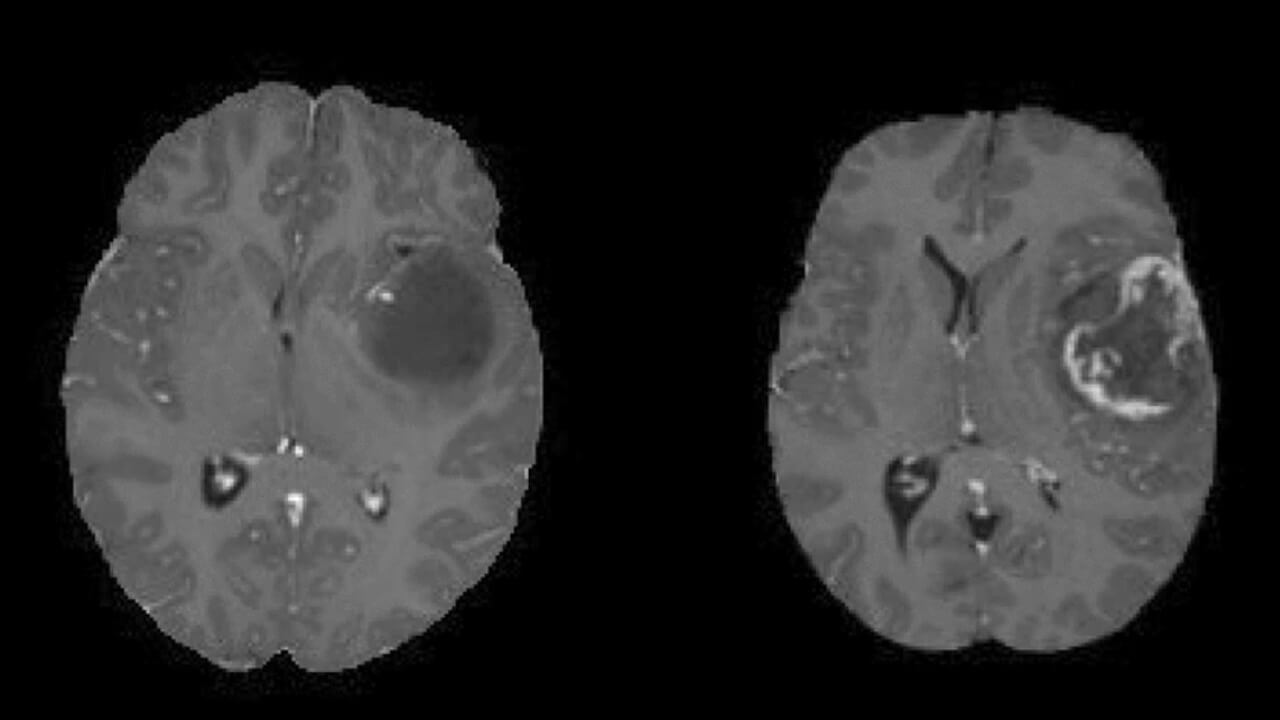

The next step in brain tumor diagnosis is imaging studies. Magnetic resonance imaging (MRI) is the most sensitive for brain tissue. It can show the tumor’s size, shape, and location, help determine whether the tumor involves vital structures, and guide surgical planning. It will help to determine the stage of brain tumor cancer. A CT scan can also be performed as the initial test when a patient presents with acute symptoms, such as a severe headache or neurological deficits.